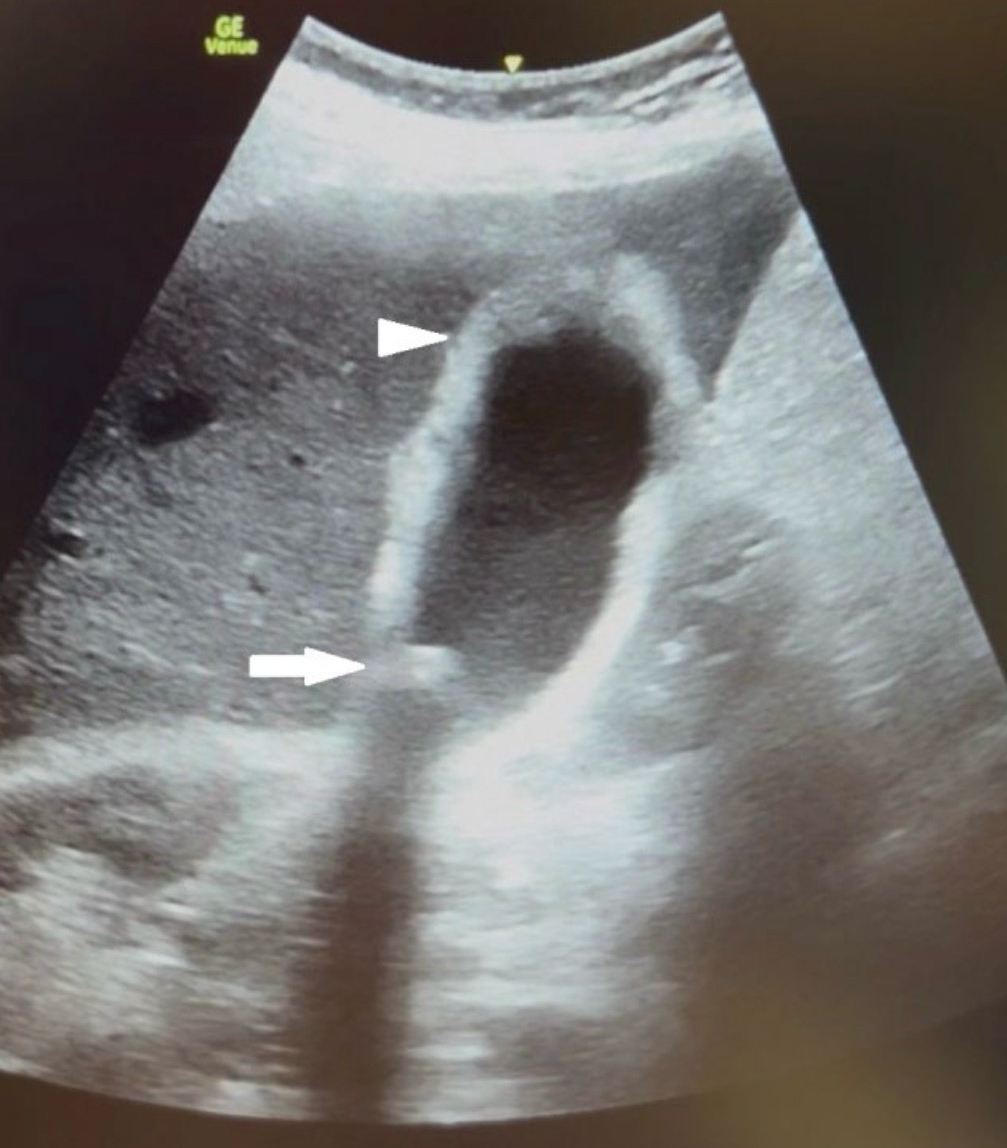

× 10⁹/L), elevated C-reactive protein (CRP) (193.9 mg/L), thrombocytopenia (133 × 10⁹/L), slightly elevated creatinine (114 μmol/L), and elevated total bilirubin. (31.3 μmol/L) and direct bilirubin (11.8 μmol/L). Within 20 minutes of arrival, a POCUS of the abdomen was performed, which showed an enlarged gallbladder (>10 cm) with a thickened and irregular wall (>5 mm), a concretion in the neck of the gallbladder with positive sonographic Murphy’s sign (Figure 1).

Figure 1. Pocus of the gallbladder showed an enlarged gallbladder (>10 cm) with a thickened and irregular wall (>5 mm) (white arrowhead) with a concretion in the neck of the gallbladder (white arrow)